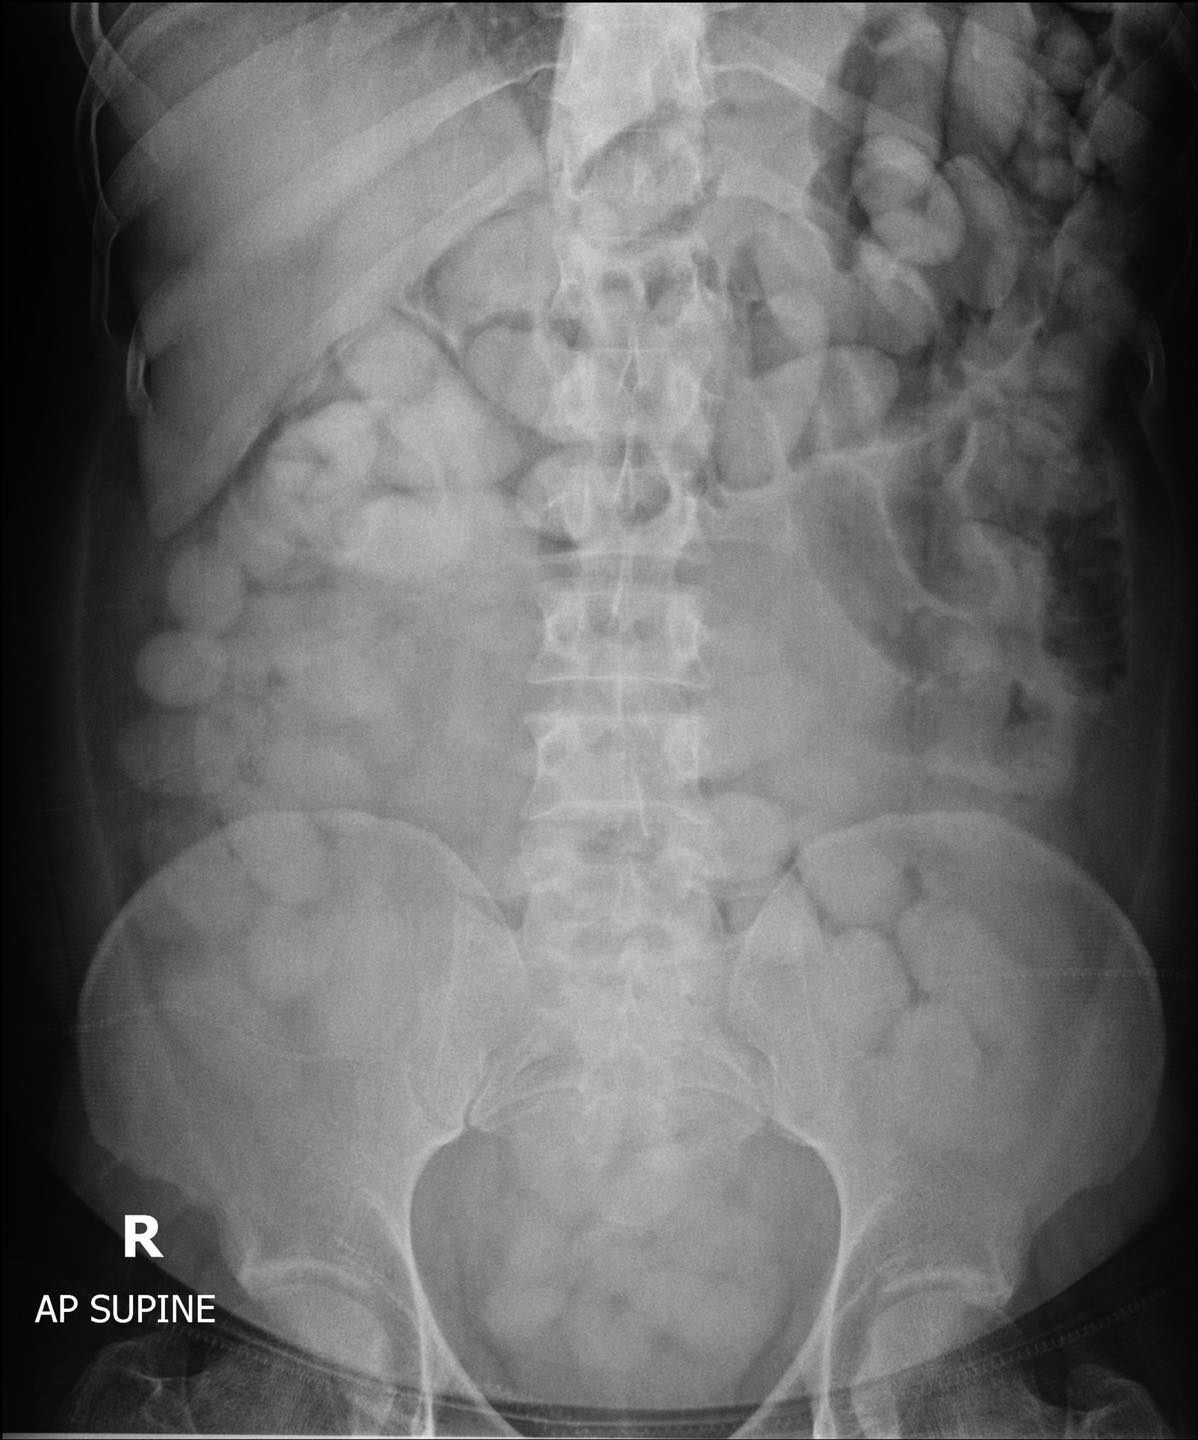

海关总署署长Chaiyut Kumkun昨天表示,这名29岁的南非男子于6月9日从埃塞俄比亚的亚的斯亚贝巴抵达普吉岛后,行为可疑。虽然在他的行李中没有发现非法物品,但该男子被拘留并被送往普吉岛的塔朗医院接受检查,经过X光检查显示他体内有115粒可卡因。